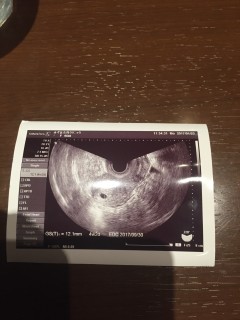

最終月経開始日1/18。3/6に陽性。3/7胎嚢見えず。3/15に胎嚢確認、7ミリ。次は2週間後に診察!心拍確認できますように!